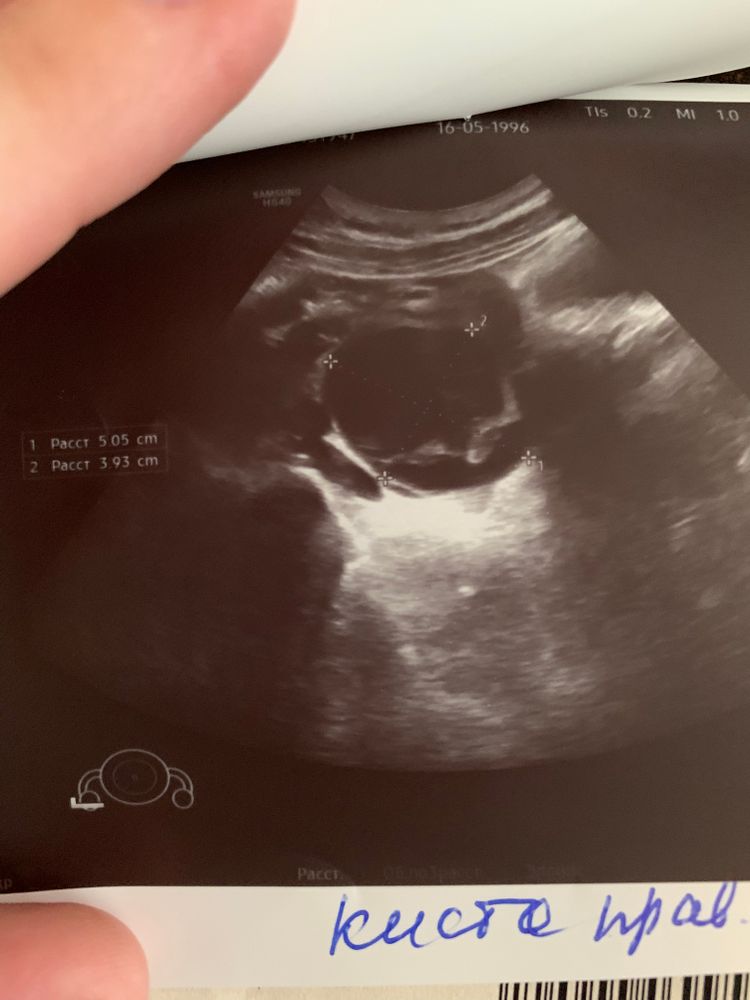

Ходила сегодня на УЗИ другого органа, но обнаружили кисту на правом яичнике 5х3.9, сказали, что функциональная, либо образовалась из желтого тела, либо из фолликула (скорее всего, это была первая овуляция после беременности)

Делала узи по женски 7 апреля (8д.ц) кист не было